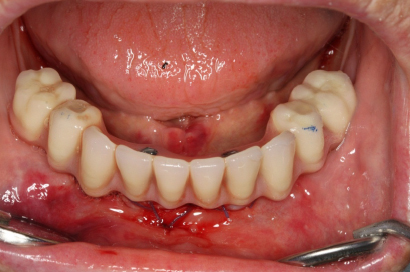

Během let může postupnou ztrátou zubů zůstat v ústech omezený počet zubů, které umožňují držení zubních náhrad.

V důsledku přetížení zbylých zubů např. houpavými pohyb snímacích náhrad dochází k uvolnění těchto zubů a držení můstků a protéz je tak velmi těžké. V těchto případech můžeme pomocí implantátů zvýšit počet pilířů a tím zabránit přetěžování a ztrátě zbylých zubů

> zpět k možným příkladům ošetření